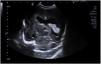

A male 24 was born at 246/7 weeks of gestation. Newborn weighed 540g and Apgar score 4/6/7. He was intubated in the delivery room due respiratory effort and during the first hours of life received endotracheal surfactant. Child remain stable without need of inotropic support and FiO2 of 25%. According to the unit protocol was monitored with a cerebral near-infrared spectroscopy (NIRS) and at 36h there was a sudden drop from values of 80 to 40. Diagnosis of shock was made and inotropic support and increase in ventilator settings. A cranial point of care ultrasound revealed a real time bilateral bleeding from the germinal matrix-intraventricular hemorrhage (videoclip 1 available online, Supplementary Fig. 1) with blood inside both lateral ventricles and the occipital horns (Figs. 1 and 2). Emergency transfusion was given and NIRS improved to 75 allowing to decrease inotropic support and respiratory support.